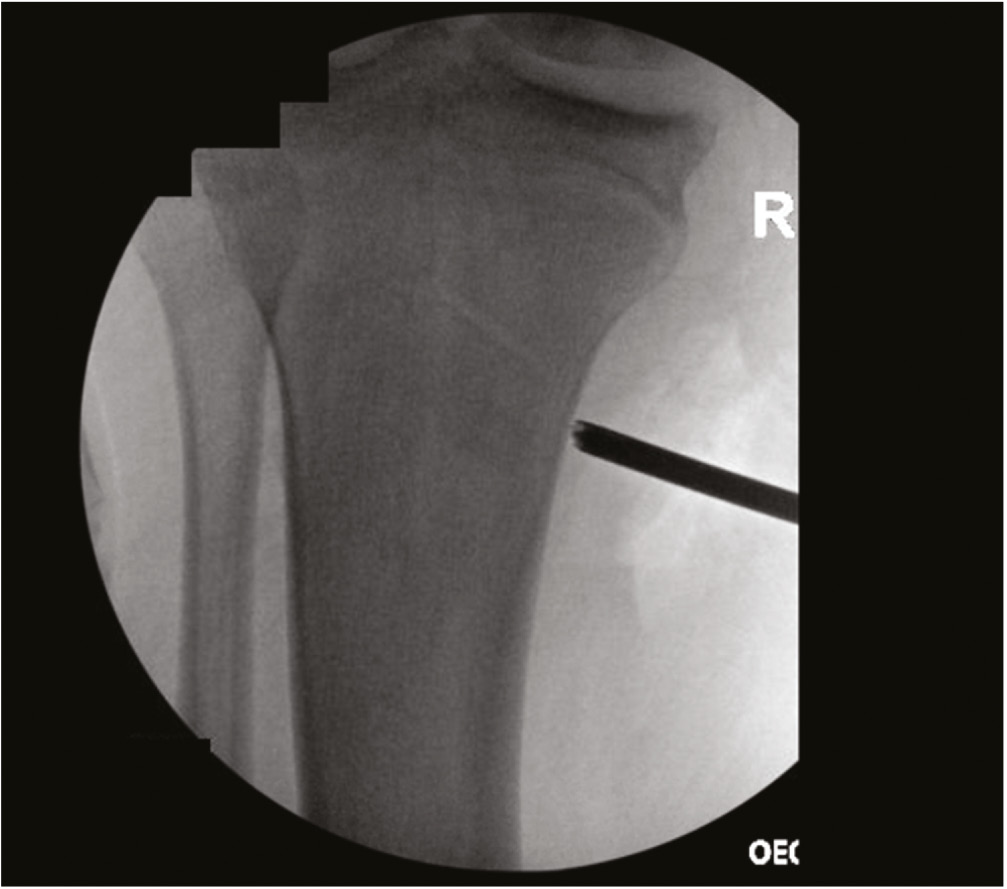

Stress radiographs have become increasingly important in the workup and management of medial-sided knee injuries. These radiographs help objectively assess the extent of the medial-sided injury. While established thresholds exist in the adult population, these have not been validated in pediatric patients. Stress radiographs are performed with the practitioner applying a valgus stress to the extremity with the patella pointed towards the ceiling and the knee flexed 15-30 degrees (Figure 6). The uninjured contralateral extremity is also imaged and serves as a comparison. It is usually more successful to begin imaging the uninjured extremity to decrease anxiety associated with obtaining these stress images on the injured leg. Additionally, timing the stress maneuver with the radiographer minimizes the amount of time stress is held. Most patients tolerate these stress views without significant discomfort. The gapping between the medial femoral condyle and the medial tibial plateau is measured and compared to the uninjured extremity (Figure 7).

Figure 6. Technique for performing valgus stress radiographs.

Figure 7. Valgus stress radiographs of a patient with a complete tear of the superficial MCL seen with a 3 mm side-to-side difference between the left and right knees.